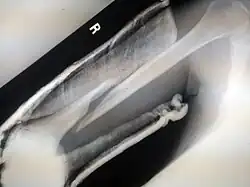

![]() |

Spiral fracture or torsion fracture | At least one part of the bone has been twisted (image shows an arm-wrestler) | Torsion on the bone[37] | May rotate, and must be reduced to heal properly |